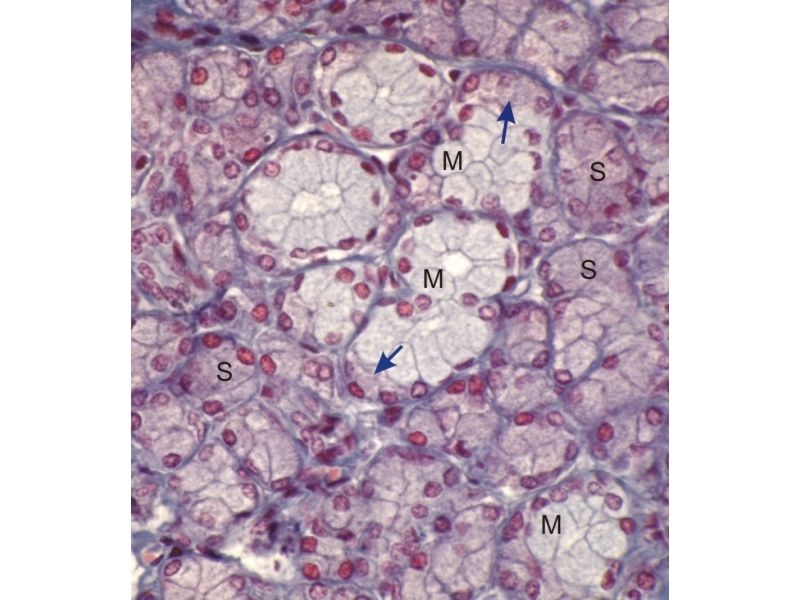

Fill in all the missing labels, and assess as you move through the slides. Answers on the down slide. It is important to do this using pen and paper, and not just glance through the images.